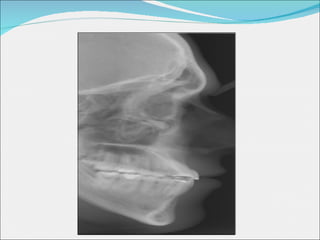

Estudi de diferents casos Problema estètic Sistema Damon Mecànica convencional Problema funcional Sistema Damon Mecànica convencional

PROBLEMA FUNCIONAL: MECÀNICA CONVENCIONAL

Inicials Finals